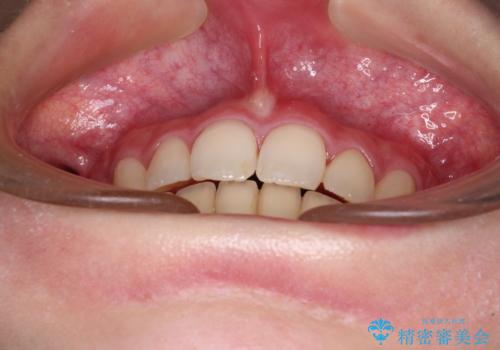

治療途中で転院 抜歯矯正の仕上げ治療

- 地元で抜歯治療を行っている途中、東京へ転職したため治療を継続して欲しいとのことで来院された患者様です。

出っ歯を抜歯矯正にて治療をしていらっしゃいましたが、抜歯スペースが少し残っていたため、閉じて歯列を仕上げていくこととしました。